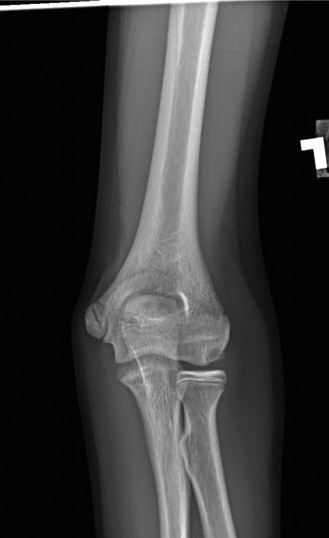

She has received multiple corticosteroid injections into her elbows over the past 3 years, but she no longer gets relief. Her images are shown (Figs. 2–99 to 2–102).

Figure 2–99

Figure 2–100

Figure 2–101

Figure 2–102

Approximately what percentage of patients with rheumatoid arthritis develop elbow involvement within 5 years?

- 10%

- 5%

- 75%

- 60%

- 40%

Discussion

The correct answer is (E). Between 20% and 50% of patients with rheumatoid arthritis will develop elbow arthritis. Isolated presentation of the elbow is rare and only occurs about 5% of the time. Care should be given to provide the best treatment for the entire upper extremity when evaluating and treating a patient with rheumatoid arthritis.

Which of the following is the procedure of choice when treating an advanced, debilitating rheumatoid elbow?

- Elbow arthrodesis

- Open synovectomy

- Radial head excision

- Arthroscopic synovectomy

- Semi-constrained total elbow

The correct answer is (E). Semi-constrained total elbow is the definitive procedure of choice when treating an elbow with extensive articular damage and subluxation or ankylosis of the joint (see Fig. 2–103). Rheumatoid patients place a lower demand on the prosthesis than patients with primary osteoarthritis (OA), and thus have a lower incidence of mechanical loosening. Due to the ligamentous laxity, prosthetic instability is the complication that most commonly inhibits success.